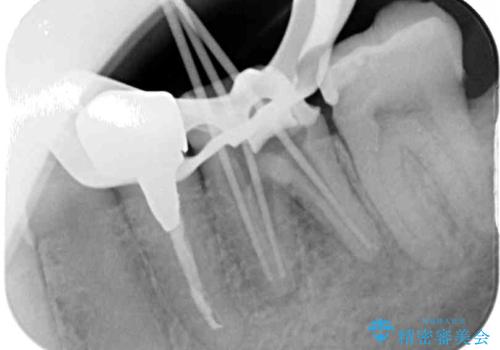

- 下顎左右の奥歯を治療途中で放置してしまっているとのことで来院された患者様です。

欠損部はインプラントによる補綴治療を、土台の外れてしまった歯は、根管治療を行った上で、補綴治療を行うこととしました。